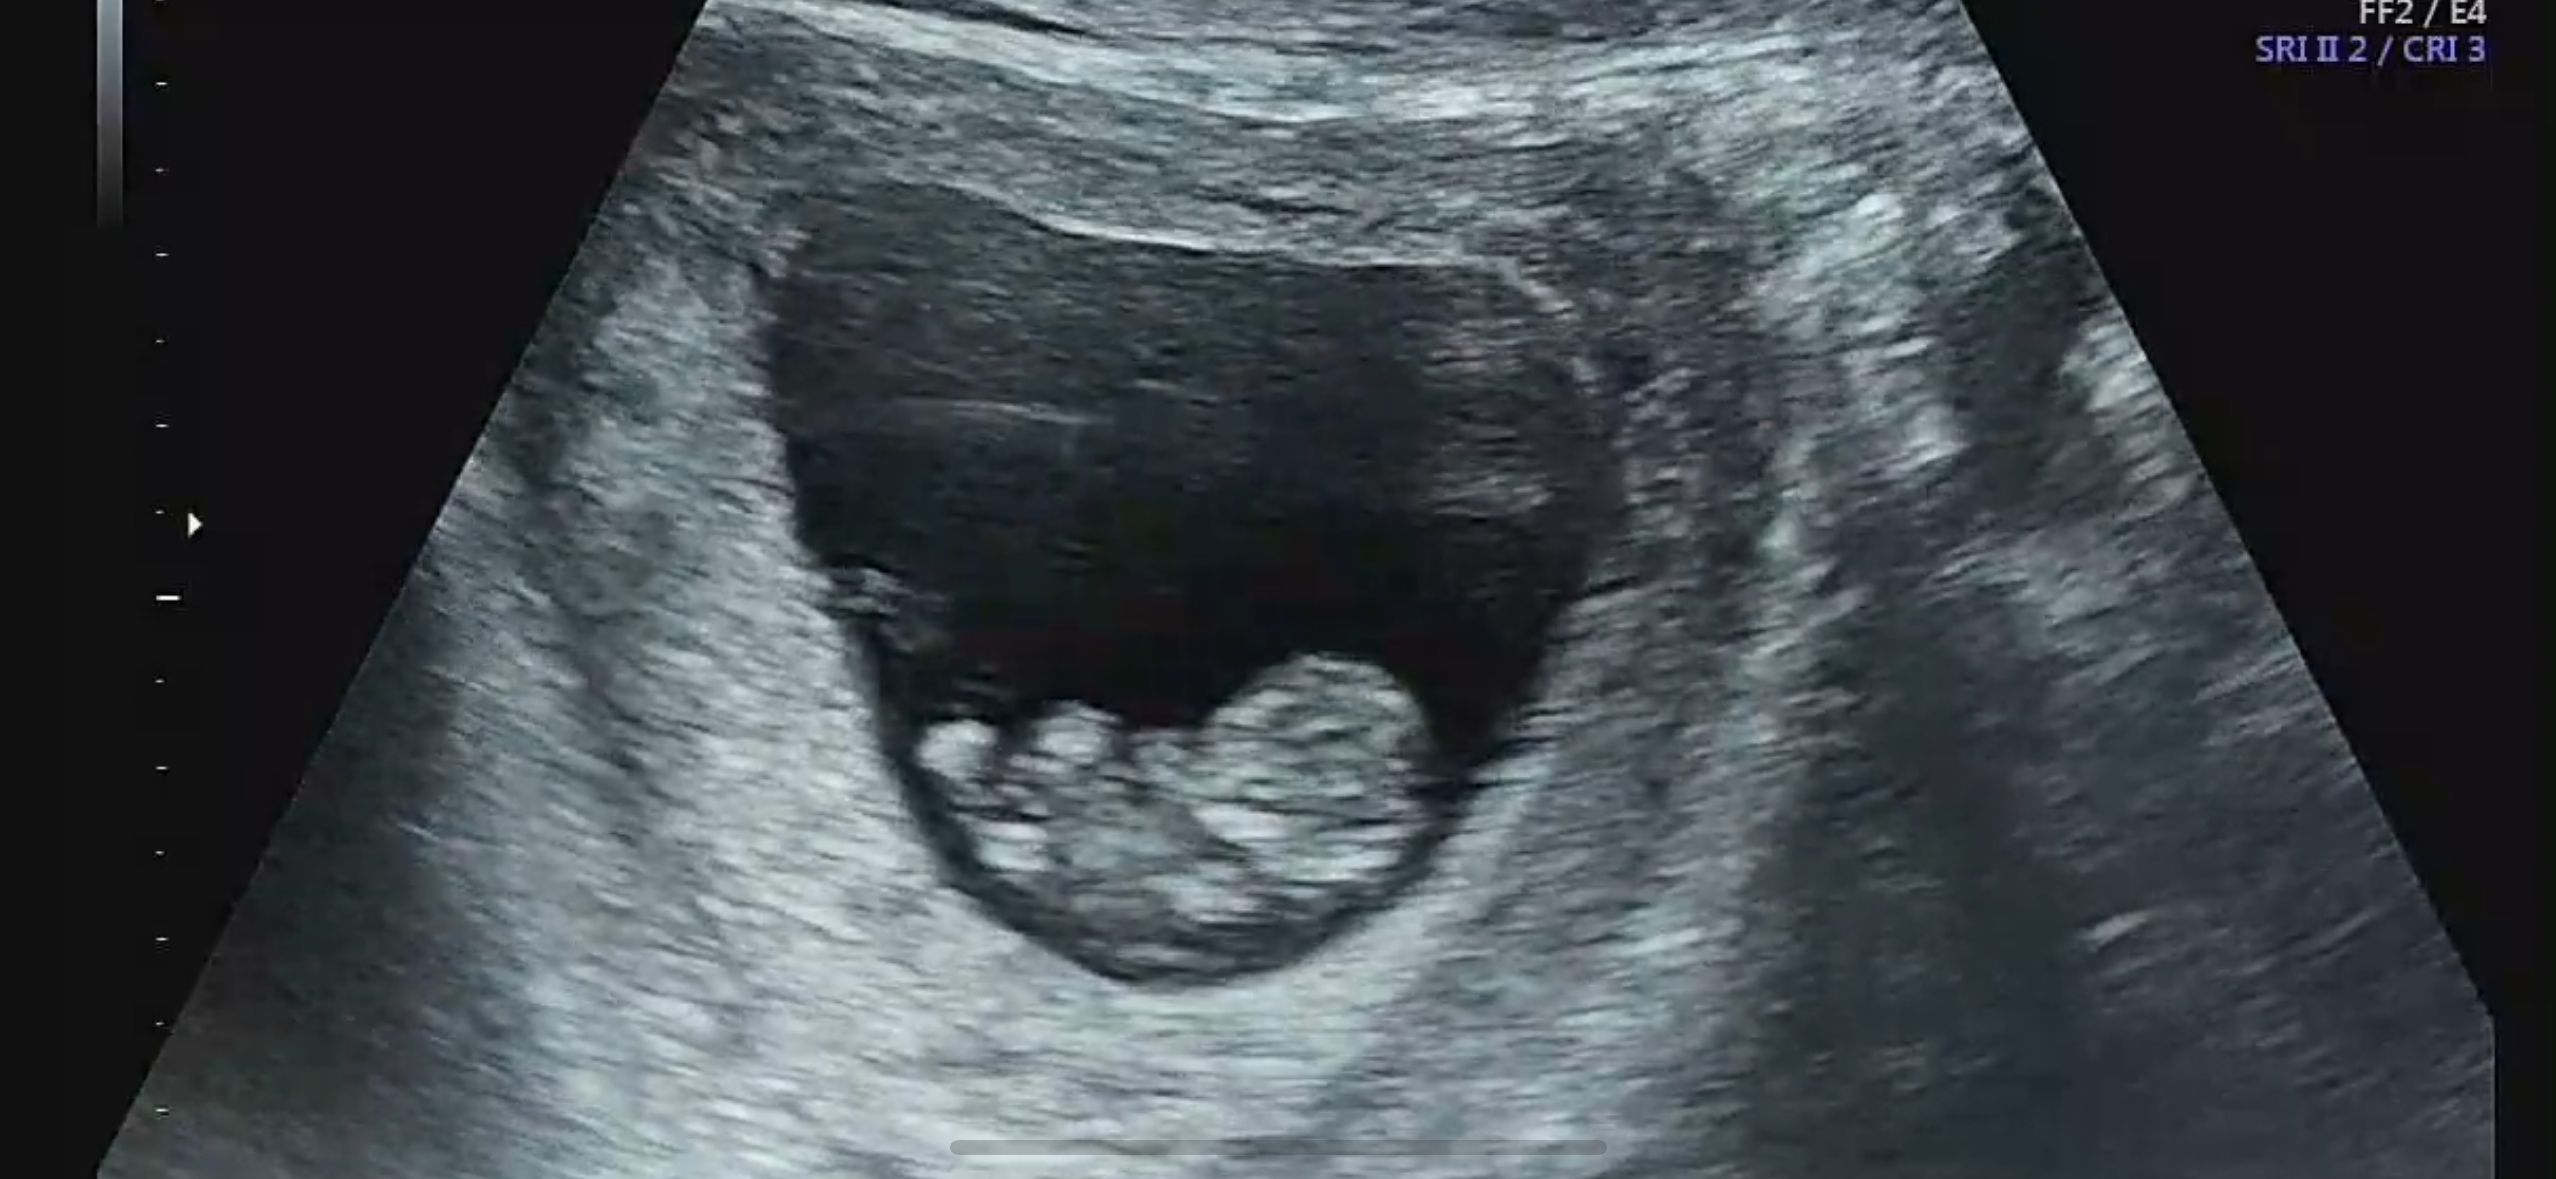

탯줄이 이렇게 잘 보이나요?

꼬리 달린 꼬북이 같아요 ㅎㅎ 9주 4일차 초음파 젤리곰 보고왔어요! 7주차에 계류유산 했었어서 아직 많이 무서운데 빨리 12주 지나면 좋겠어요

초음파에 탯줄은 계속 잘 보여요 늘 탯줄이 생식기 부분을 가리고 있었어요 ㅎㅎ